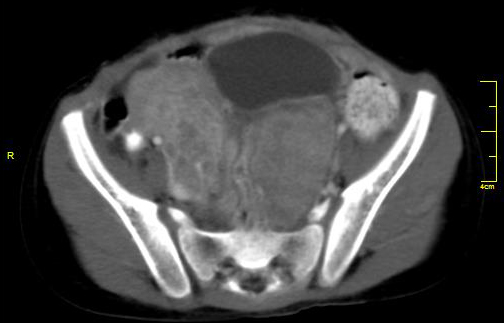

Metastases constitute about 5-15% of ovarian masses. Stomach, colon, breast, pancreas and lung are the most common primaries. Krukenberg tumours are ovarian metastases with mucus filled signet ring cells. They display bilateral, oval/ lobulated solid or predominantly solid with central necrosis. On CT/MR they show strong contrast enhancement. Non Krukenberg metastases appear similar to primary ovarian malignancy. They are usually bilateral and may be solid and cystic or complex lesion; may be multilocular and associated with ascites. Omental cake represents replacement of normal fat of omentum by a soft tissue density and the causes include peritoneal metastasis from carcinoma of colon, ovary, pancreas, stomach and breast and also from lymphoma, mesothelioma and tuberculosis of the peritoneum (Figures 18 & 19).

Figure 18: Krukenberg tumour from carcinoma of the breast.

Figures 19: 23y/F – Mucinous adenocarcinoma of stomach with deposits on ovaries - Krukenberg tumour.